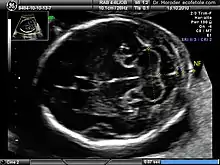

Nuchal scan (NT procedure) is performed between 11 and 14 weeks of gestation, because the accuracy is best in this period. The scan is obtained with the fetus in sagittal section and a neutral position of the fetal head (neither hyperflexed nor extended, either of which can influence the nuchal translucency thickness). The fetal image is enlarged to fill 75% of the screen, and the maximum thickness is measured, from leading edge to leading edge. It is important to distinguish the nuchal lucency from the underlying amniotic membrane.[8]

Normal thickness depends on the crown-rump length (CRL) of the fetus. Among those fetuses whose nuchal translucency exceeds the normal values, there is a relatively high risk of significant abnormality.